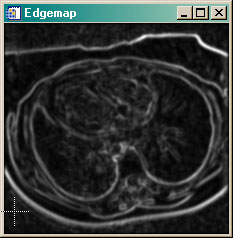

| Edgemap |

At the heart of the GVF active contouring method is an edgemap. This is the gradient of the image scaled into the range of 0 to 1. What you should see in the edgemap image are the edges of the image. The edgemap is used to calculate the external forces on the contour in the GVF algorithm The active contour is 'pushed" or "pulled" toward the image edges. |